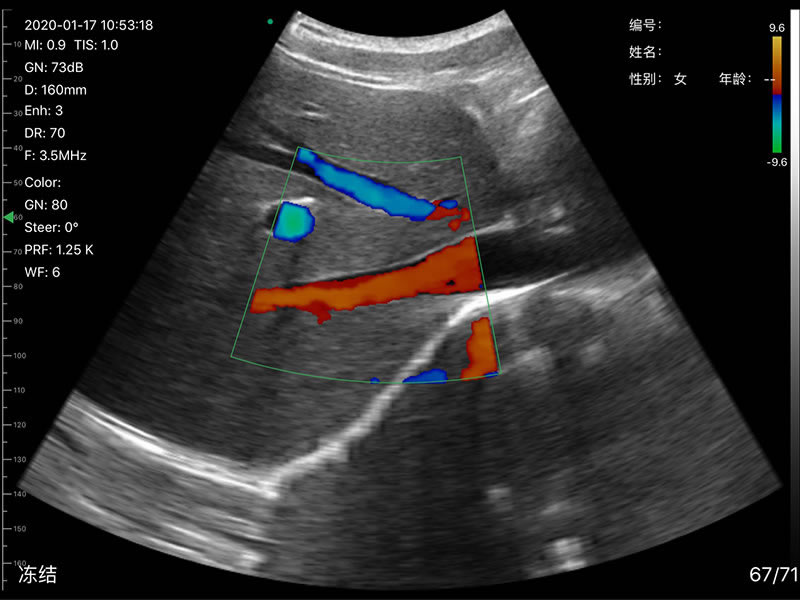

• Frequency: R60 Convex/Phasedarray probe 3.2MHz/5MHz,

• Display Depth: Convex 90/160/220/305mm, Linear 20/40/60/80mm

• Scan angle and width: convex 60°, Phasedarray 80°, linear 40mm